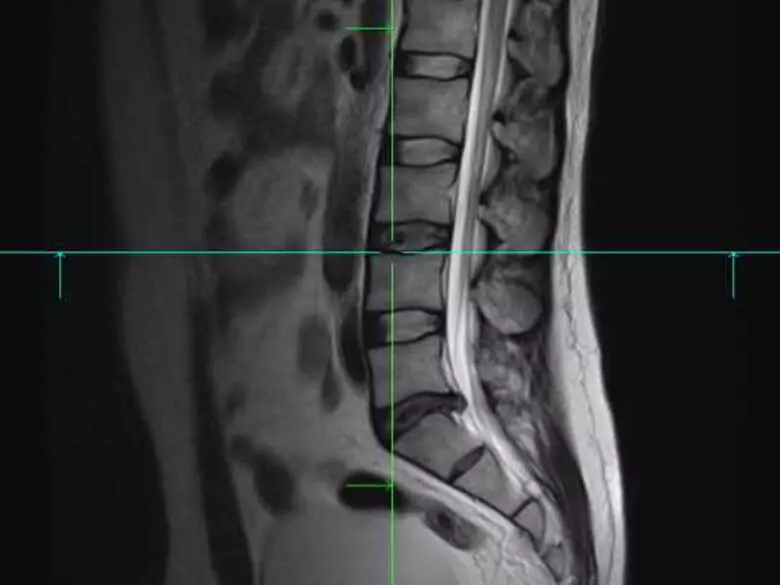

Eine Diskopathie ist nichts anderes als der Vorfall einer Bandscheibe aus ihrem Platz, ihrer natürlichen Position. In den meisten Fällen betrifft die Diskopathie die untere Wirbelsäule (sakrale und lumbale Segmente).

Diskopathie